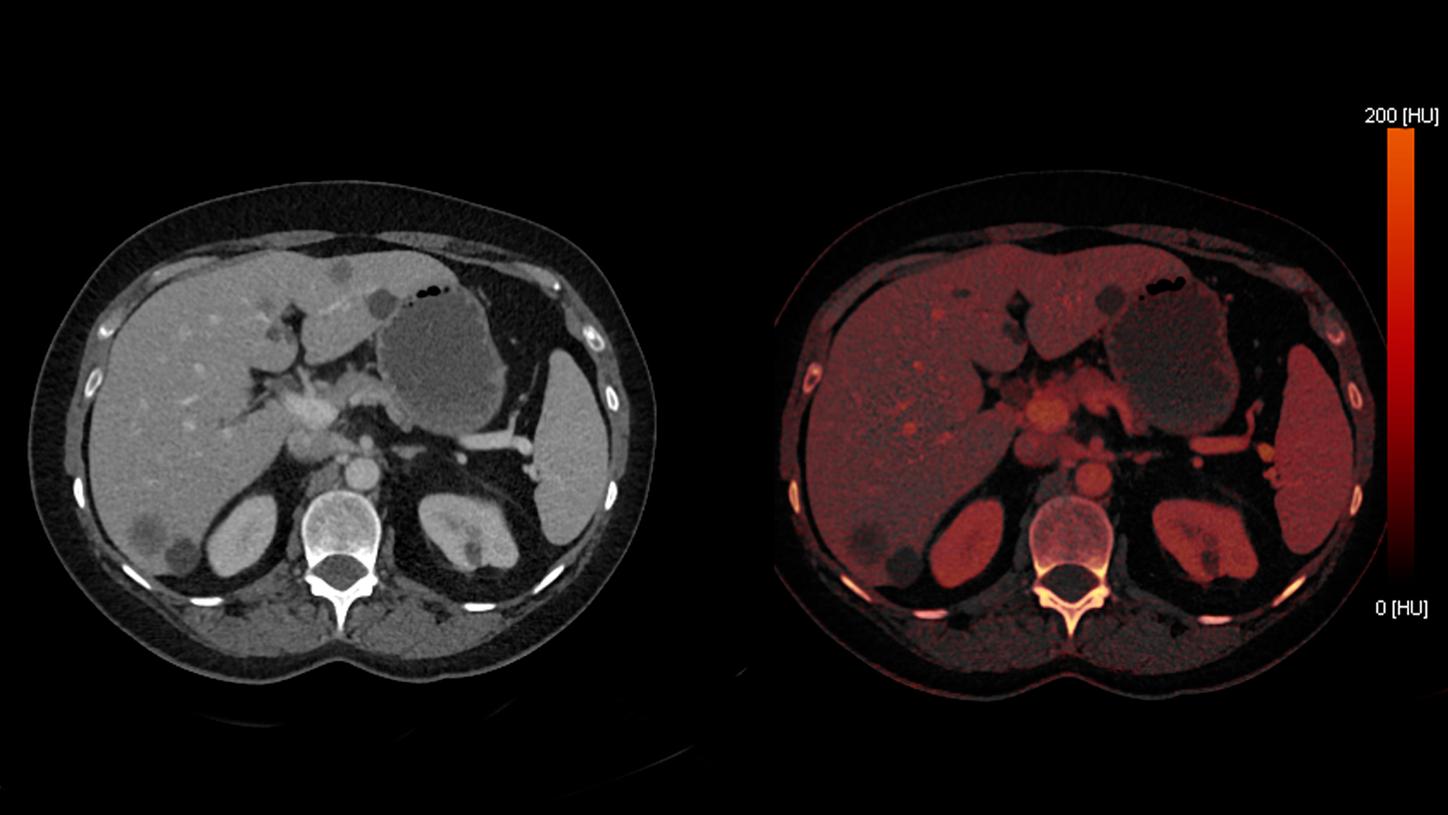

A 54-year-old female patient with breast cancer, post-lumpectomy status, underwent thoracoabdominal CT for the assessment of metastatic disease. A contrast-enhanced TwinBeam Dual Energy (TBDE) CT was performed.

Differentiation of Liver Metastases from Benign Cysts